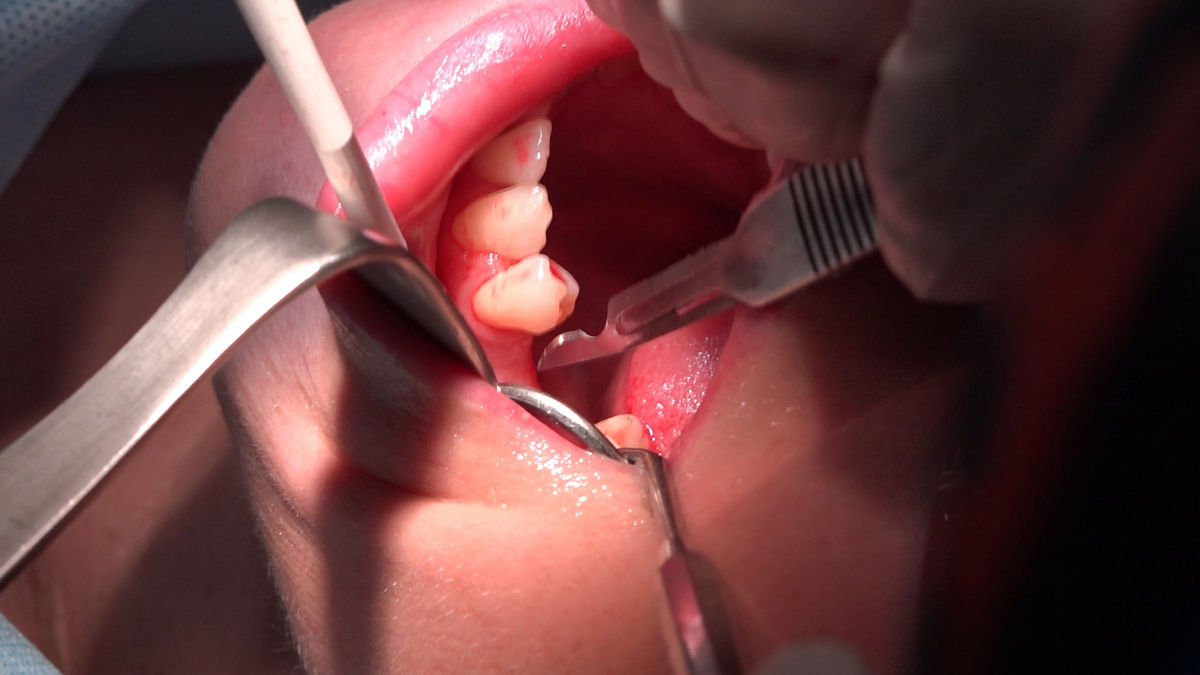

Chirurgia implantologiczna to temat wiodący 5 Sesji X Sezonu Practiculum Implantologii, która się odbyła 23-24 października 2020 roku. Bierze w nim udział 16 adeptów implantologii stomatologicznej. Zabiegi z udziałem Pacjentów jak zwykle poprzedziło omówienie i planowanie, tym bardziej, że zgodnie z planem wykonana została implantacja z wykorzystaniem szablonu chirurgicznego, który przygotowało laboratorium dentystyczne Wiligała Lab. Kursanci wykonywali szereg zabiegów implantologicznych i chirurgicznych oraz regeneracyjnych z zastosowaniem PRF, w tym sinus lift. Przeprowadzali je pod kierunkiem Lidera Umiejętności Implantologicznych dr n.med. Violetty Szycik, która wysoko oceniła wykonanie zabiegów.